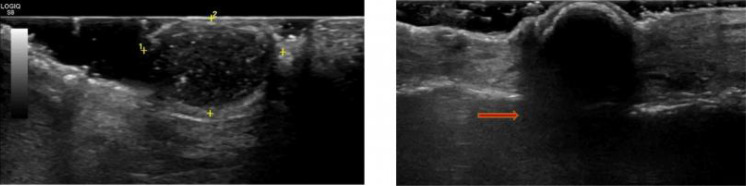

Background: Idiopathic scrotal calcinosis is a rare and benign disease of the scrotal skin that presents as solitary or multiple painless calcified nodules or papules in the absence of systemic disorders of calcium or phosphorus metabolism. Although some theories have been proposed as to the cause of this rare disease, the exact cause remains unknown. In a resource-poor medical setting like Nigeria, a confident diagnosis of this condition can be made with ultrasonography.

Case presentation: This is a case report of a 38-year-old man who presented with recently discharging but longstanding multiple painless scrotal nodules of 22-years duration.

Conclusion: This case illustrates the prompt and accurate diagnosis of idiopathic scrotal calcinosis using an ultrasound, a readily available imaging modality in a low-resource setting.Although histology remains the gold-standard for diagnosing idiopathic scrotal calcinosis following surgical excision, this benign disorder has unique sonographic characteristics that could aid the radiologist in making a confident diagnosis.